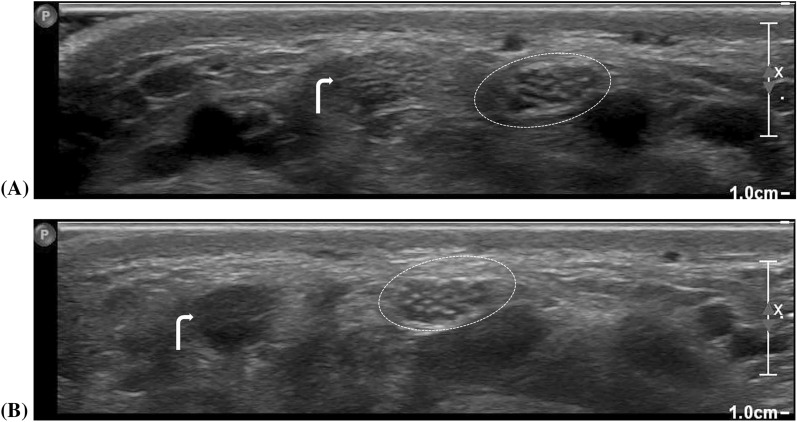

Abstract Image